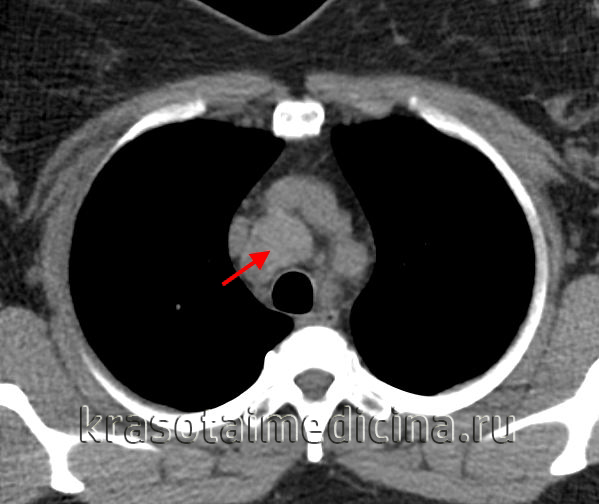

(б) У этого же пациента при КТ с контрастным усилением визуализируется мягкотканное объемное образование, прорастающее правую и заднюю стенки трахеи и распространяющееся на прилежащие отделы средостения. При бронхоскопической биопсии был выявлен плоскоклеточный рак. Распространение опухоли на прилежащие отделы средостения свидетельствует о ее злокачественности. (а) У пациента с аденоидно-кистозной карциномой при КТ с контрастным усилением определяется циркулярное утолщение стенки верхних отделов трахеи. Некоторые новообразования трахеи и бронхов, например аденоидно-кистозная карцинома, могут проявляться утолщением стенки, а не объемным образованием в просвете.

(б) Пациент с мультифокальной аденоидно-кистозной карциномой, подтвержденной при биопсии. При нативной КТ визуализируются множественные мягкотканные узелки и объемные образования, выступающие в просвет трахеи. Следует отметить различные характеристики контура: от неровного до дольчатого. (а) У пациента с аденоидно-кистозной карциномой при нативной КТ на реконструкции в коронарной плоскости в правой стенке трахеи определяется мягкотканный узелок с четким дольчатым контуром. Следует отметить утолщение прилежащей стенки трахеи